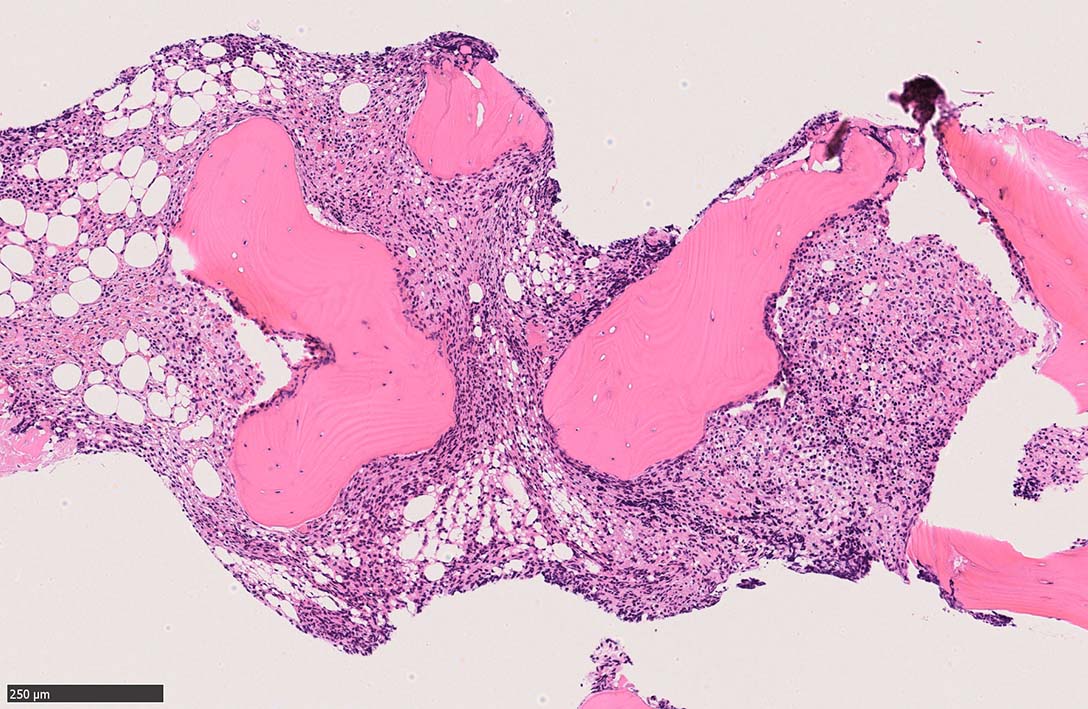

骨髄生検

bone marrow trephine biopsy: dry tapのため骨髄生検が行われる. cellularityは40-80%とhypercellular marrow. 流れのある細胞配列は線維化を疑わせる.

Ag染色では, 疎な弾性線維が増生し,増殖細胞を小胞巣状に分画するいわゆる「lymphomatoid pattern」を呈する. 本例では, Mgkに異形成所見がある.